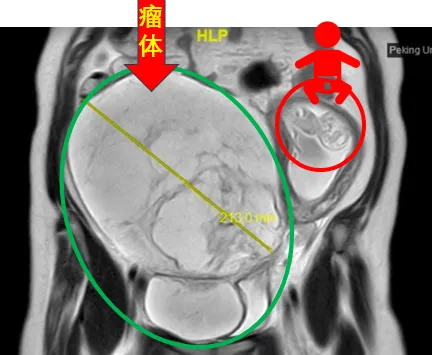

31岁的谢女士罹患静脉内平滑肌瘤病两年多,正鼓起勇气准备接受治疗时,意外发现自己怀孕了。在孕期激素的“加持”下,谢女士盆腔内的瘤体迅速增大至足月胎儿大小,血管内瘤栓沿着右侧髂静脉、下腔静脉一直“爬”到右心房,甚至在心脏舒张期进入右心室,使她处于随时可能猝死的高危风险下。

▲2024年4月,谢女士的核磁共振图像显示,巨大肿瘤将她的子宫挤到了腹腔左侧